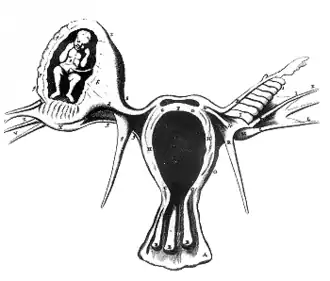

Un embarazo ectópico (del gr. ἐκ, "fuera", y τόπος, "lugar") es una complicación del embarazo en la que el óvulo fertilizado o blastocito se desarrolla en los tejidos distintos de la pared uterina,[2] ya sea en la trompa de Falopio (lo más frecuente), en el ovario, en el canal cervical, en la cavidad pélvica o en la abdominal. Cuando el embarazo ocurre en el endometrio del útero se le conoce como embarazo eutópico.[3] Las señales y síntomas incluyen típicamente dolor abdominal y sangrado vaginal, pero menos de 50 % de las mujeres afectadas muestran ambos síntomas.[4] El dolor puede también extenderse al hombro si ha ocurrido sangrado al interior del abdomen.[4] Una hemorragia severa puede llevar a taquicardia, desmayo o choque circulatorio.[5][4] Con muy raras excepciones, el feto es incapaz de sobrevivir. El embarazo ectópico se produce por un trastorno en la fisiología de la reproducción humana que lleva a la muerte fetal,[6][7] y es la principal causa de morbilidad fetal y materna en el primer trimestre con 2 o 3 semanas del embarazo.[8]

En general, los embarazos ectópicos afectan cada año a menos del 2 % de embarazos en todo el mundo.[5] Factores de riesgo para un embarazo ectópico incluyen la enfermedad pélvica inflamatoria, a menudo debida a una infección por clamidias, fumar tabaco, endometriosis, cirugía tubárica previa, una historia de infertilidad y el uso de tecnología reproductiva asistida.[9] Las mujeres que han tenido previamente un embarazo ectópico se encuentran en un riesgo mucho más alto de volver tener uno.[9] La mayoría de embarazos ectópicos (90%) ocurren en las trompas de Falopio, y son conocidos como embarazos tubáricos,[9] pero la implantación puede ocurrir también en el cuello uterino, los ovarios, la cicatriz cesárea o dentro del abdomen.[4] La detección de un embarazo ectópico se hace generalmente con pruebas sanguíneas en las que se evalua la presencia de gonadotropina coriónica humana, así como con ultrasonido.[4] Esto puede requerir que el examen se lleve a cabo más de una vez. Otras causas de síntomas similares incluyen el aborto espontáneo, torsión ovárica y apendicitis aguda.[4]

Cuando ocurren, los embarazos ectópicos suelen desarrollarse en una de las trompas de Falopio (embarazo tubárico). Son infrecuentes los embarazos en el canal cervical, en el ovario o en la cavidad abdominal o pélvica. Un embarazo ectópico constituye un riesgo para la vida, por lo que debe ser interrumpido lo antes posible. Según algunas estadísticas, 1 de cada 826 mujeres con embarazos ectópicos muere por complicaciones. En España se estima que el embarazo ectópico constituye aproximadamente el 2,3 por ciento del número total de embarazos.[3]